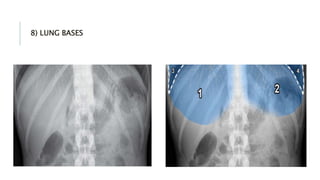

8) LUNG BASES

LUNG BASES

•Metastasis :

rounded

opacities

projected over

•Consolidation :

patchy

opacification.

•Large pleural

effusion/

collapse :

whiteout